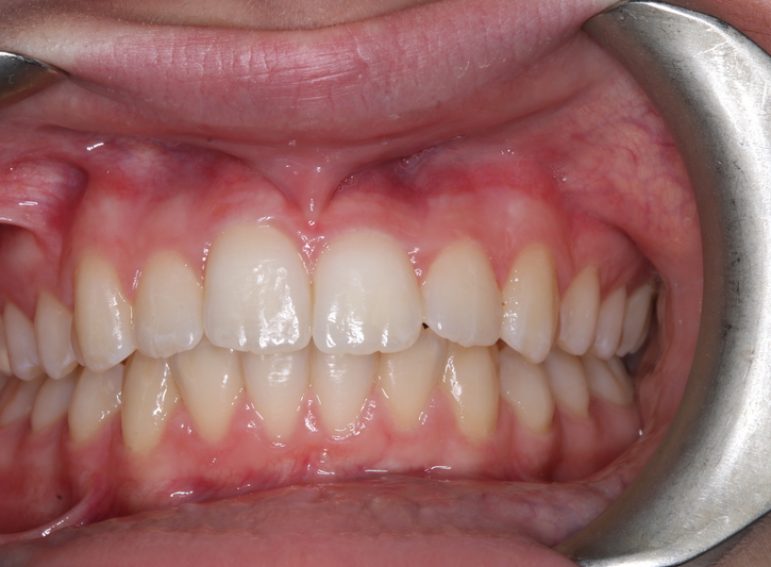

Case 5 – Dental Trauma

Severe Intrusion during braces